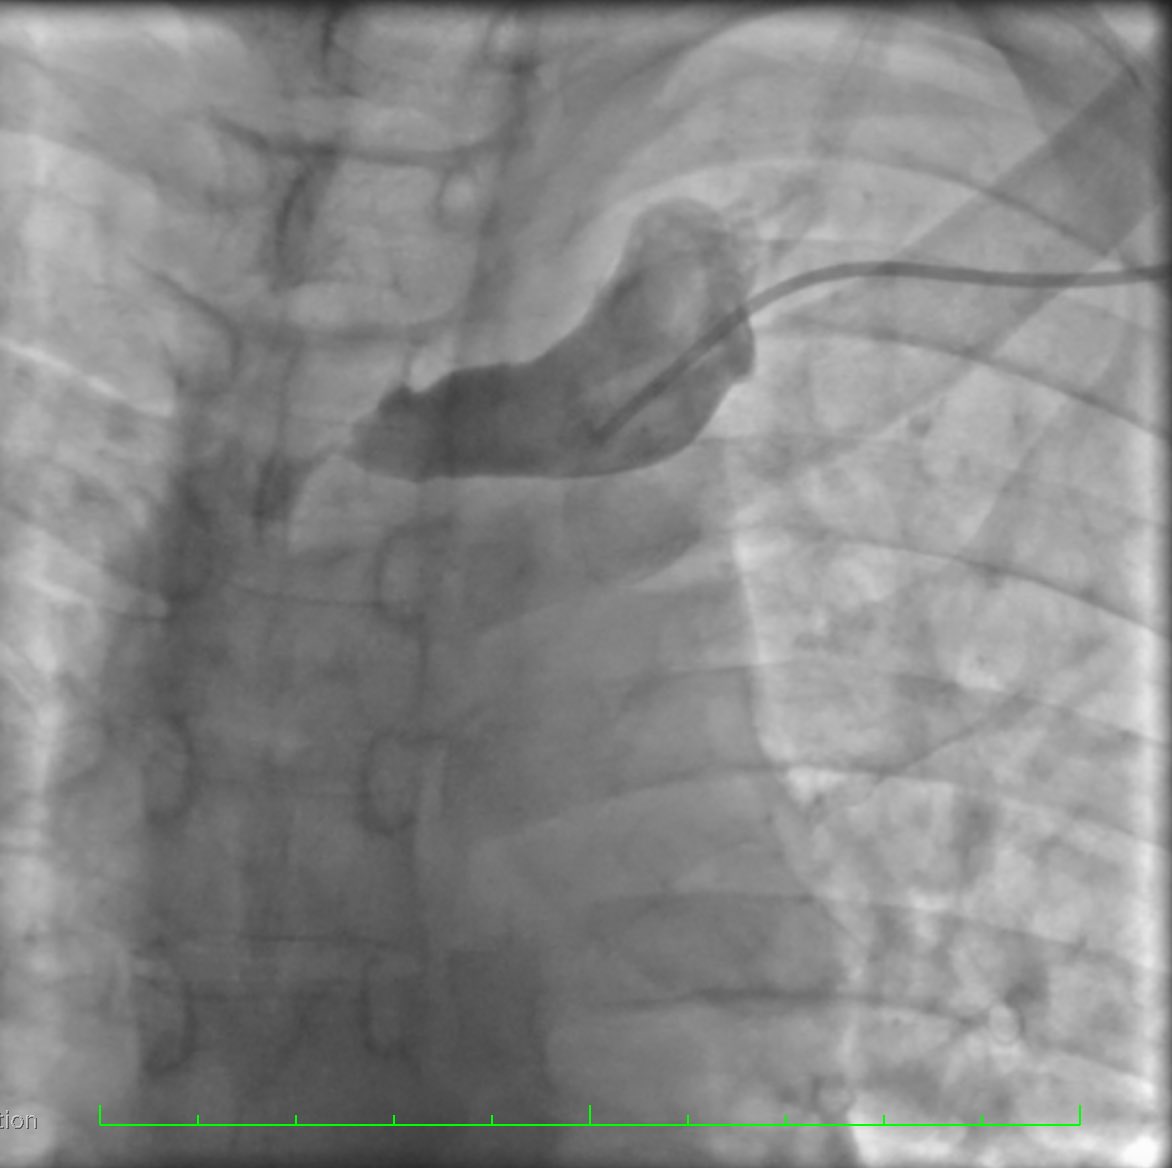

Colocación de Catéter Tenckhoff percútaneo con técnica Seldinger Servicio de Nefrología HGR 46 ✅Menor estancia hospitalaria ✅Menor riesgo de complicaciones ✅Uso temprano de cavidad peritoneal